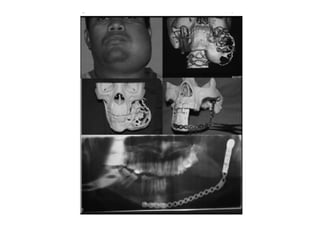

2. CT scan in case of larger lesions and esp maxillary

ameloblastoma

 RECONSTRUCTION:

1. For the mandible, segmental defects of 5 cm can

be reconstructed with bone grafts most commonly

iliac crest.

2. For more larger defects free osseofasiocutaneous

flaps may be used.. DCIA and free fibular flap.

3. Reconstruction plates are used as adjuncts to

grafts or as an interim treatment modality